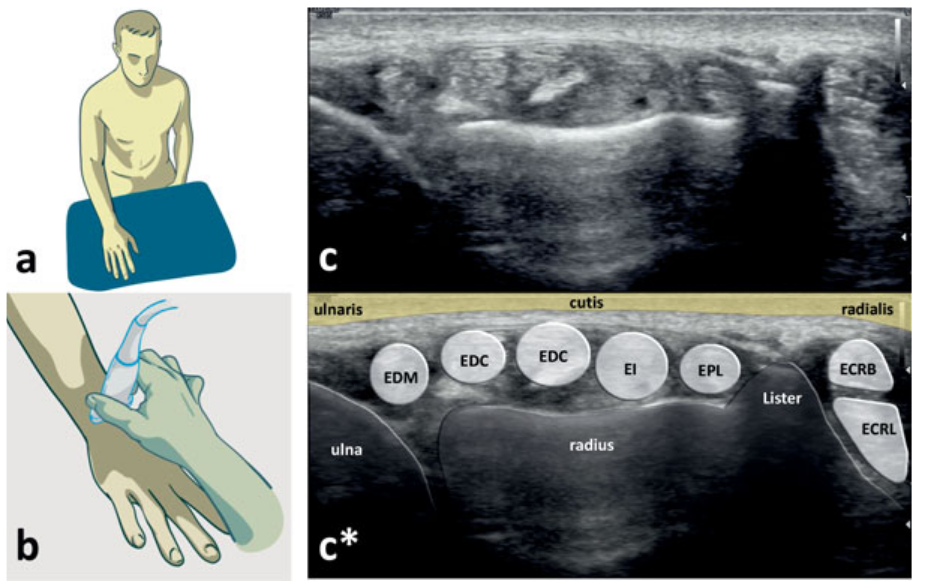

Ultrazvukové vyšetření hlezenního kloubu

Kapitola o vyšetření hlezenního kloubu ultrazvukem z knihy „Praktická muskuloskeletální ultrasonografie pro lékaře a fyzioterapeuty“

HRAZDIRA, Luboš. Praktická muskuloskeletální ultrasonografie pro lékaře a fyzioterapeuty: Praktická muskuloskeletálna ultrasonografia pre lekárov a fyzioterapeutov. Brno: Paido, 2020. ISBN 978-80-7315-270-3.